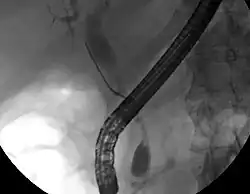

Cholangiokarcinom

Cholangiokarcinom je maligní onemocnění extrahepatálního žlučovodu pocházející ze soutoku levého a pravého jaterního kanálu do spodního konce společného žlučovodu. Mezi příznaky patří bezbolestná cholestatická žloutenka, moč tmavě žlutá nebo hnědá, stolice světlá, mírné bolesti v horním břiše po jídle, bolesti v zádech, horečka (většinou způsobena zánětem žlučovodu).